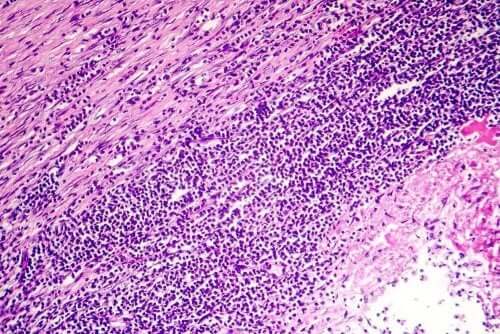

Приблизно у 80% випадків встановити причину перикардиту неможливо. Однак дуже часто він є наслідком якоїсь інфекції. Дуже ймовірно, що це вірусна інфекція. Може бути бактеріальна інфекція, але з меншою імовірністю, і лише дуже рідко це може бути наслідком грибкової інфекції.

Так само є багато випадків, коли перикардит супроводжує будь-яке з цих захворювань:

- аутоімунні захворювання

- рак, включно з лейкемію

- СНІД

- ниркова недостатність

- гіпотиреоз

- туберкульоз

- ревматична лихоманка

В інших випадках це прямий результат серцевого нападу, кардіохірургічного втручання або травми грудної ділянки. Іноді перикардит може виникати внаслідок запалення міокарда, променевої терапії грудної клітки або використання певних препаратів.